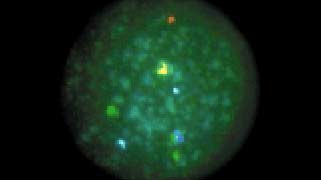

1313q14.2Vysis LSI 13 SpectrumRed           3VIEW IMAGE

2121q22.13-q22.2Vysis LSI 21 SpectrumGreen            2VIEW IMAGE

2222q11.2Vysis LSI 22 SpectrumGold             5VIEW IMAGE